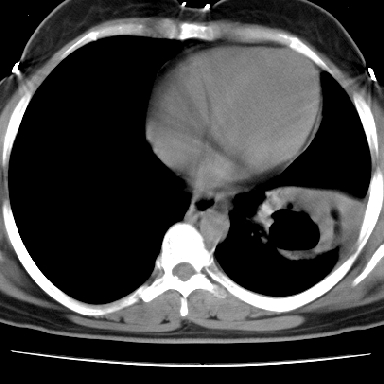

左下肺有空洞,壁厚薄不均,壁结节,两肺多发小结节影,腋窝下可疑淋巴结肿大,综上所述考虑周围性肺癌并两肺转移可能性大,建议穿刺活检。

右肺多发小结节影,边界清楚,符合转移瘤的特点;2、左下肺偏心性空洞影,右侧乳腺内高密度影,需要查体除外右侧乳腺肿瘤;3、腋窝淋巴结肿大,考虑转移。

支持癌性空洞:壁厚,无液平,内壁不规则,外壁呈分叶状,较大,偏心性,壁结节,胸膜凹陷,转移灶。